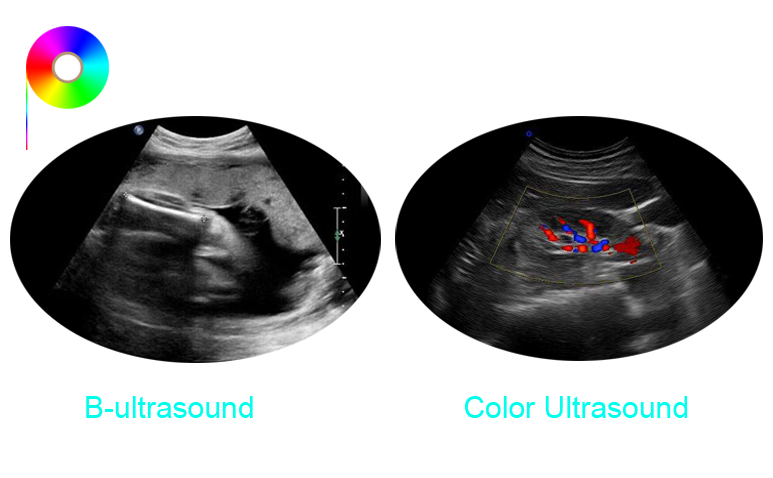

B-ultrasound and color ultrasound(also called color Doppler ultrasound) are the most basic and widely used diagnostic techniques in medical imaging examination. The working principles are the same: they are two-dimensional plan views obtained by sound wave reflection.

B-ultrasound is also called real-time two-dimensional ultrasound, which uses the difference in the absorption of ultrasound by human tissues to display the normal anatomy of the human body on the display screen. It is a black and white image. It can reflect information on different sections of the human body, and diagnose diseases such as liver and splenomegaly, common bile duct dilatation, and intrahepatic cysts based on abnormal echoes in normal tissue structures.What is a color ultrasound?

Color ultrasound is called "Color Doppler Ultrasound". The Color Doppler is a color Doppler blood flow imaging system based on B-ultrasound. That is, on the basis of B-ultrasound, the color signal is color-coded by the color processor to display the direction and velocity of the blood flow and form an image of the blood flow state. It can visually display the distribution, running, direction of blood flow, blood flow resistance and blood flow speed of blood vessels.

Therefore, the difference between B-ultrasound and color ultrasound is in the examination of blood flow. Compared with a single black-and-white B-ultrasound, color ultrasound has more functions, the clarity of color ultrasound is greater than that of B-ultrasound, and the scope of examination is wider, which can increase the accuracy of diagnosis. Ultrasound examination has been recognized as the first choice for biliary system diseases.